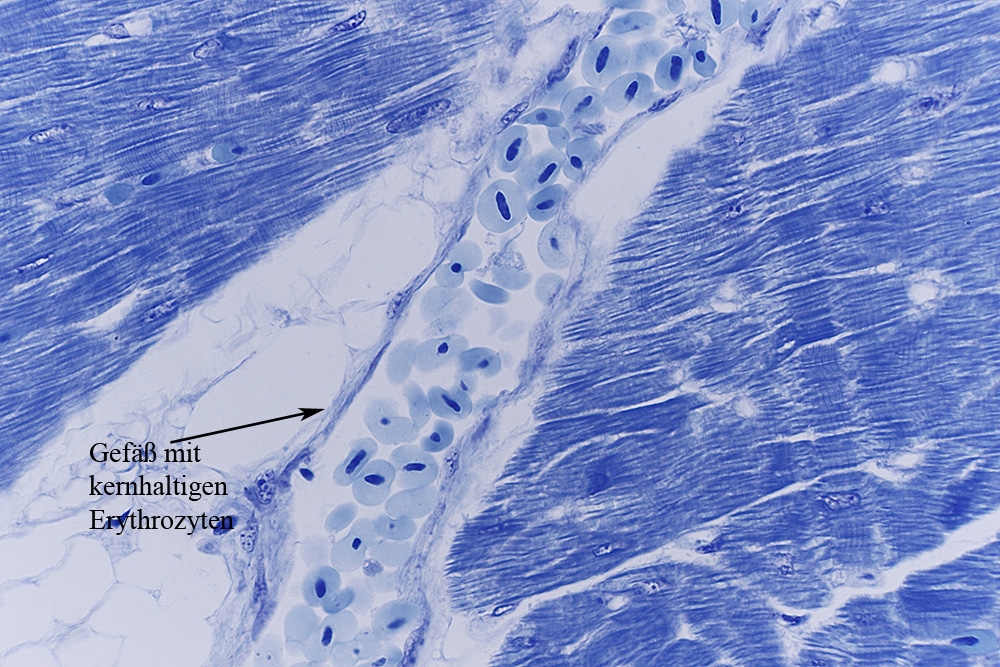

Auch lese ich das es kein Sauger ist sondern ein Huhn. Das erklärt vielleicht warum ich einige Zellen nicht erkenne.

Ich habe dein Bild 3 mal mit Pfeilen versorgt. Was sind das für welche Zellen? Weil die im Gewebe und auch im Lumen vorkommen vermute ich größere Erythrozyten die bei Vogel ja ein kern haben. Stimmt das?

Auch muss man beachten, dass die Erythrozyten beim Vogel kernhaltig sind.

Hallo Ronald,

Ja, und du hast Recht, es sind kernhaltige Erythrozyten.